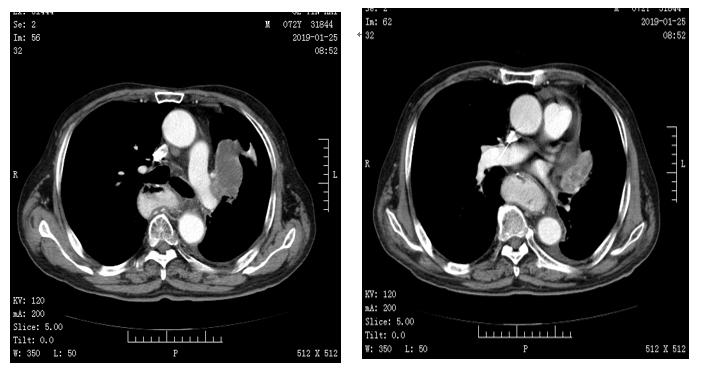

(左:2018.08.20 右:2018.10.22)且已经在服用第四疗程的援助药品,病情处于稳定,葛大爷的心情也慢慢好起来。2019-1-25号复查,病情稳定,葛大爷耐受良好目前一直在服用安罗替尼,疗效评价如下图所示:

2019年5月随访,病情稳定,结果评价:SD。

安罗替尼的疗效在葛大爷身上体现的淋漓尽致,服药过程中一直在随访其症状及不良反应。发现在开始使用安罗替尼之后,复查时肺不张的症状明显好转,原发灶也在开始时有所缩小,并且在后期疗效评价中处于SD,在服用期间的不良反应也相对较小,高血压、出血等不良反应都没有出现,乏力症状也不明显,有利于稳定患者病情,希望能使更多患者受益。